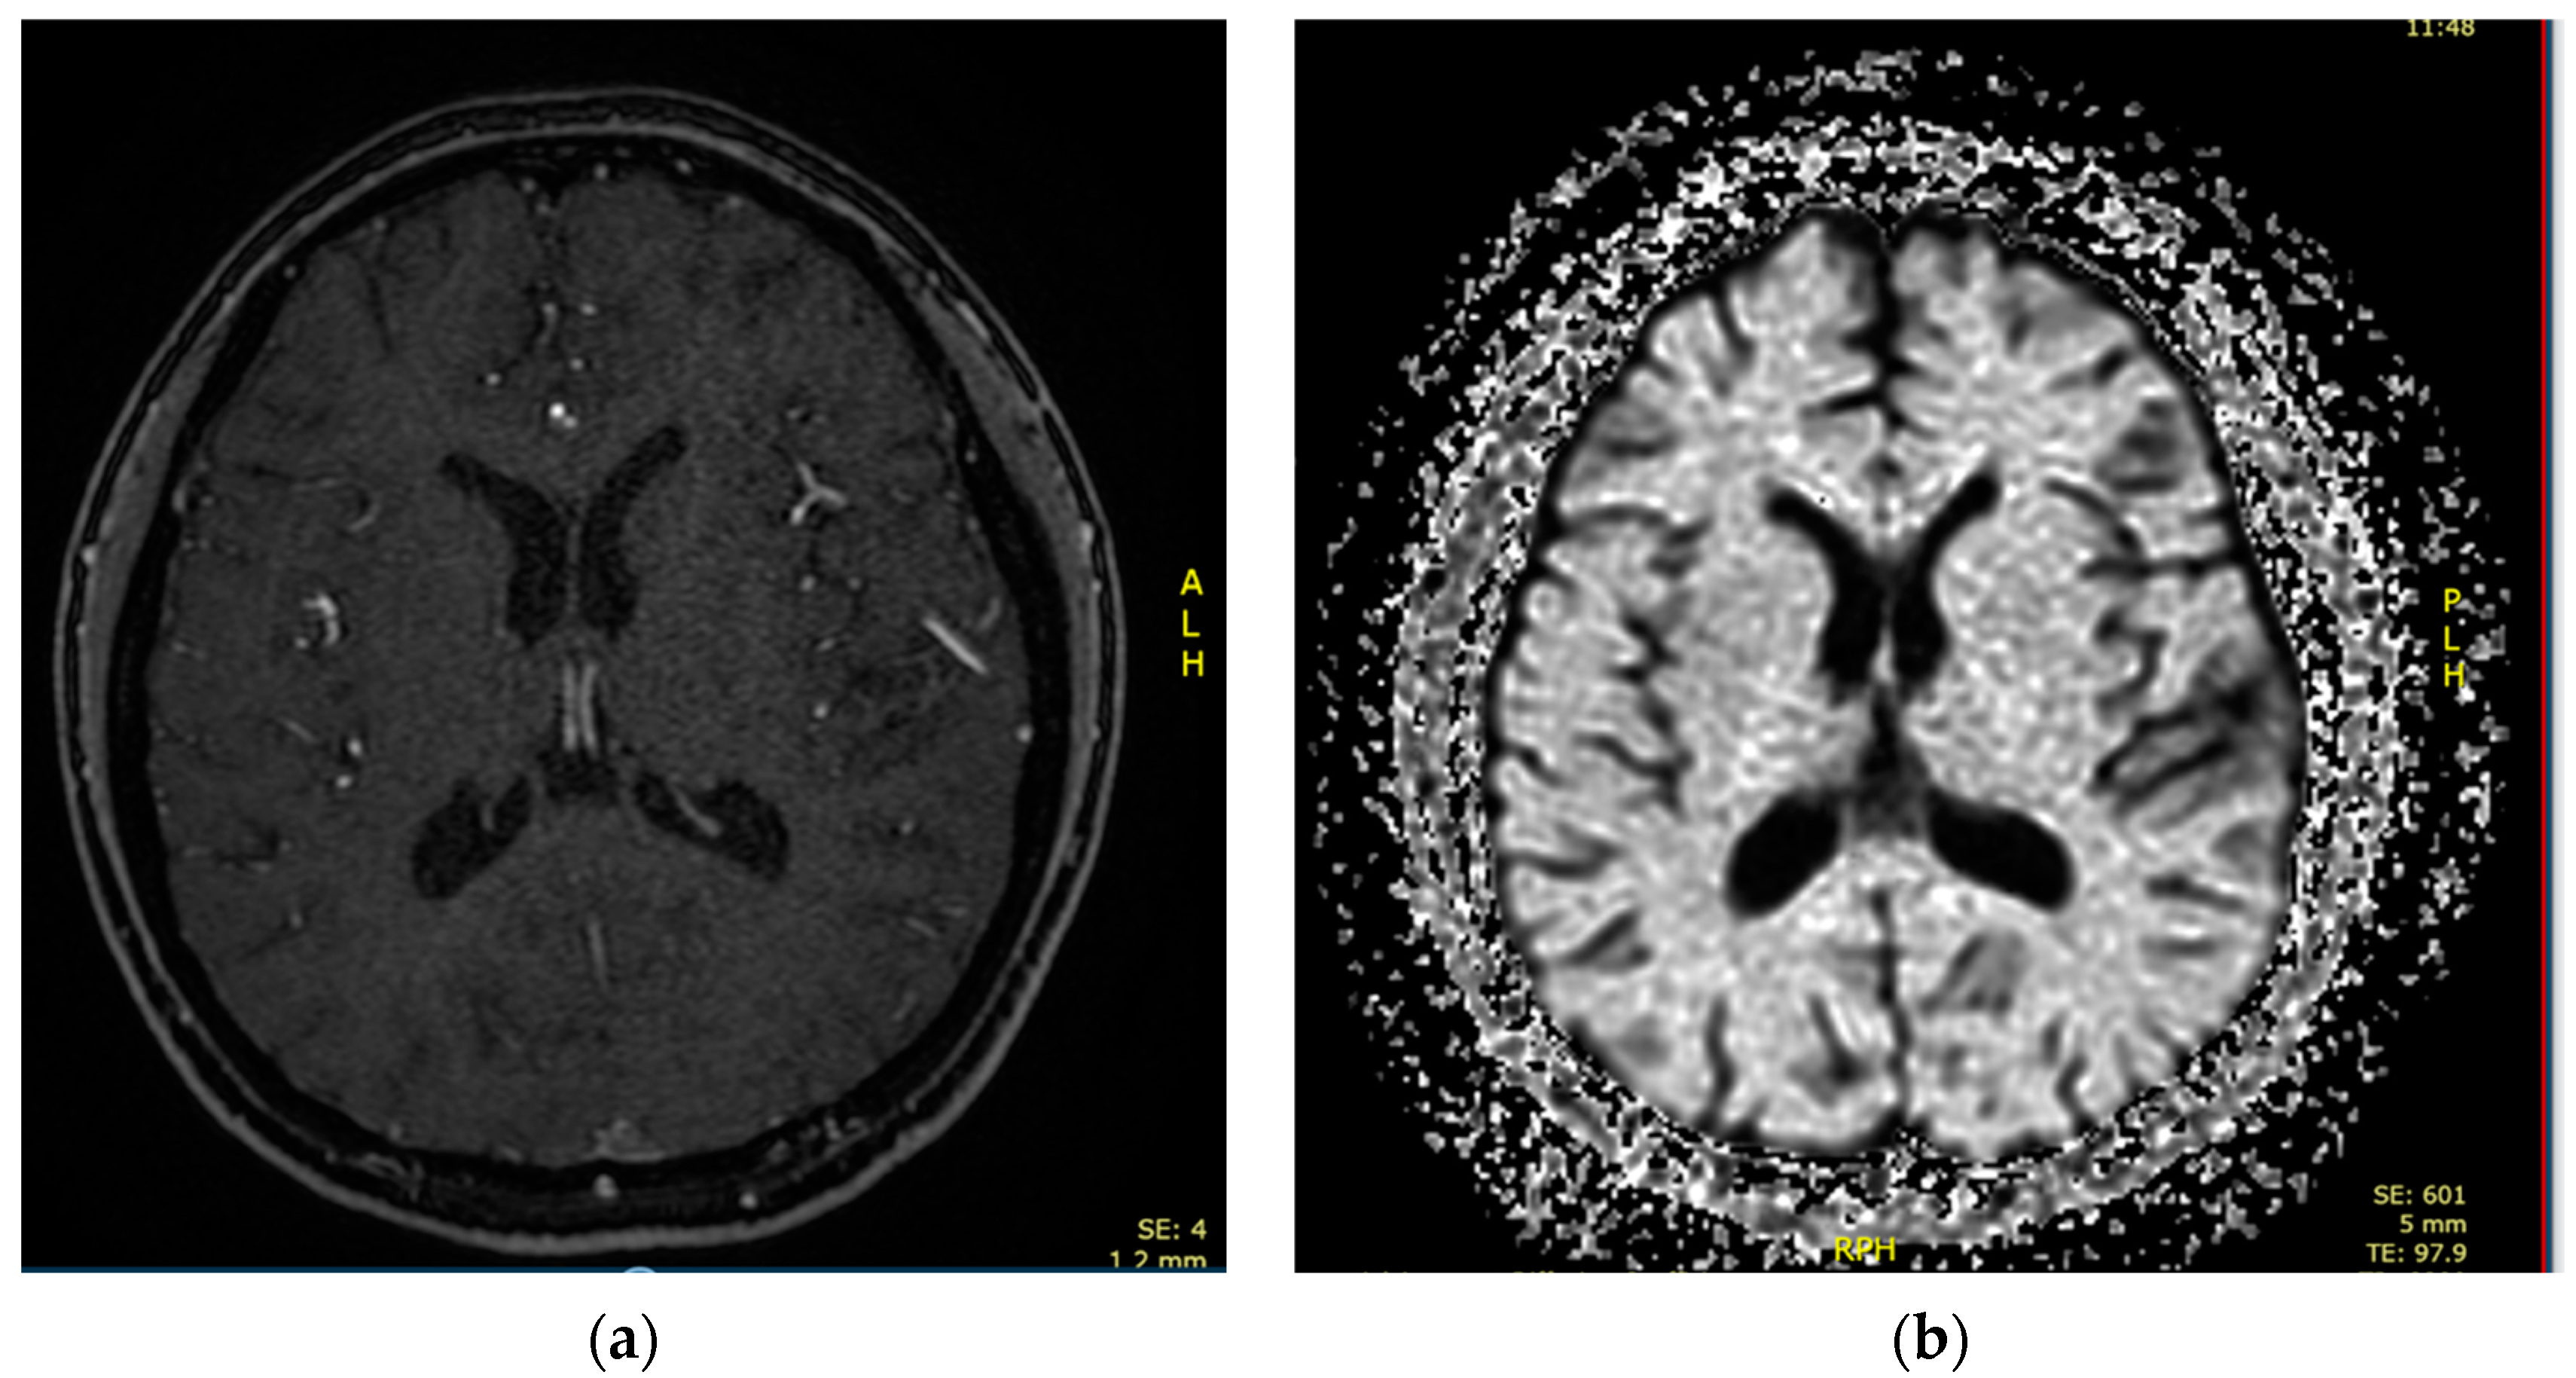

2.3. Case 3